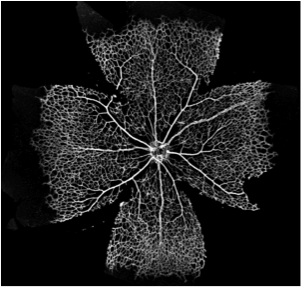

One of the pressing questions in the field is establishing how primitive vessel networks remodel into a hierarchically branched and functionally perfused network of arteries, arterioles, capillaries, and venules (Figure 1). In recent years, the main molecular mechanisms regulating endothelial cell behaviour during vessel formation have been elucidated using experimental techniques (Jones et al.,, 2006; Potente et al.,, 2011). However, important challenges remain: i) understanding how cell-level mechanisms integrate to give rise to systems-level behaviour and, ii) understanding the impact in vascular patterning of the interplay between cellular molecular regulation and haemodynamic forces (i.e. vascular mechanotransduction). These problems are hard to address due to the multiscale and multiphysics nature of the processes involved. Systems-level behaviour arises from highly non-linear, tightly coupled interactions between subprocesses at different spatial and temporal scales. Furthermore, it has been recently proposed (Bentley et al.,, 2013) that a tighter integration between experimental and computational work is required in order to tackle these questions. Working in a feedback loop, computational models should be capable of generating new hypotheses, rather than merely reproducing experimental data. In turn, experiments should provide new biological insights based on these hypotheses and help to further refine computational models.

The vascular plexus of wildtype retinas was stained with the luminal membrane marker ICAM2 and images were acquired using a confocal microscope as described in Section 33.1. Figure 5 shows a region of interest in one of the imaged retinas. It contains, on either side, two arterial segments coming from the optic disc and connecting with a segment of a retinal vein (centre of the image) through a dense capillary network. It can be appreciated how the network is more mature (e.g. vessel identity, branching patterns) closer to the optic disc (bottom of the image) while its structure is much more primitive and less remodelled in the periphery closer to the sprouting front (top of the image). Figure 5 presents the results of the image segmentation process. The algorithm described in Section 33.1 is used to first create a binary mask separating the luminal area and background tissue and second extract the network skeleton and radii. The latter are used to reconstruct the 3D luminal surface under the assumption of vessel circular cross-section (see Section 33.1 for a discussion). Figure 5 shows the reconstructed surface. We refer to this model as P6A.

Figure 6 presents luminal surface binary masks for three additional P5 and P6 retinal plexuses. The same reconstruction algorithm is applied and the resulting models are referred to as P5A, P5B, and P6B, respectively.